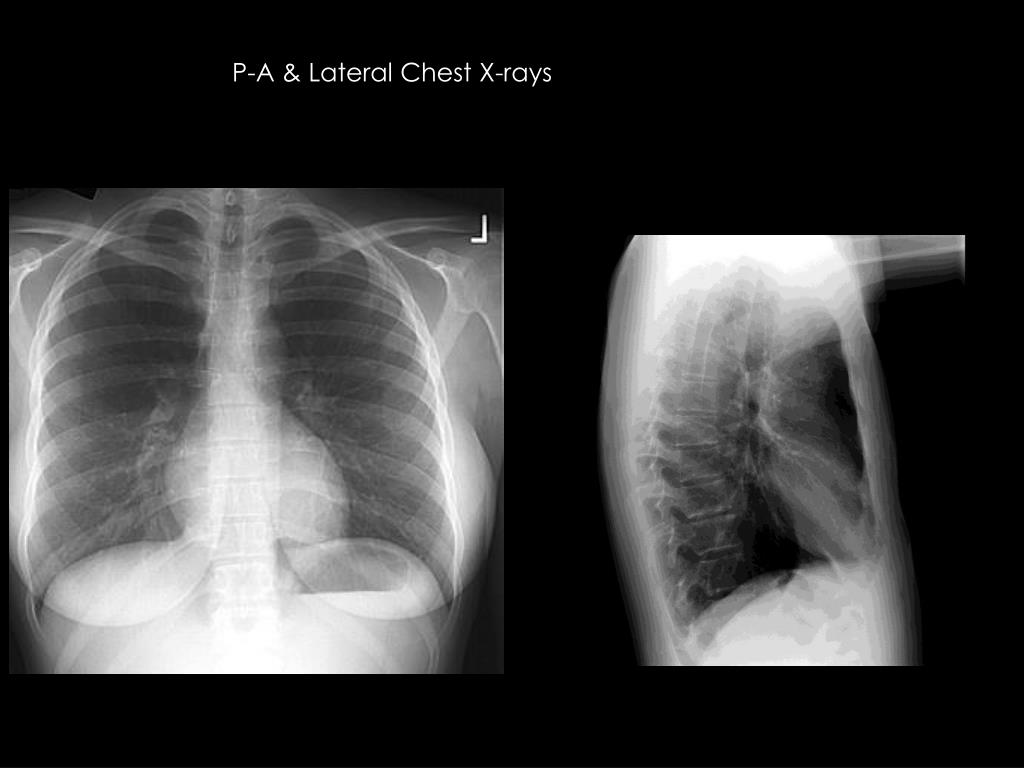

2. P-A & Lateral Chest X-rays